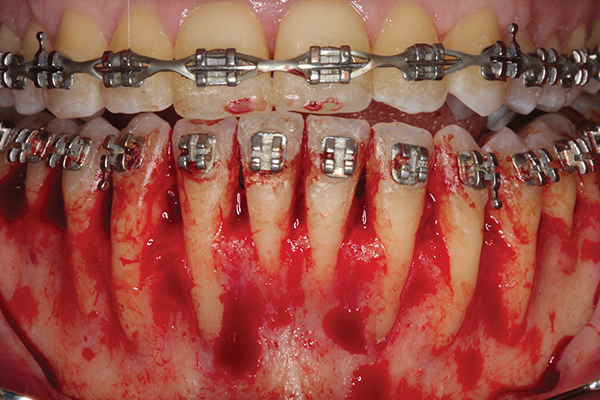

Fig 2. Full-thickness flap reflection. Note

dehiscence and fenestrations throughout. Orthodontic walls are limited to nonexistent.

Figure 2